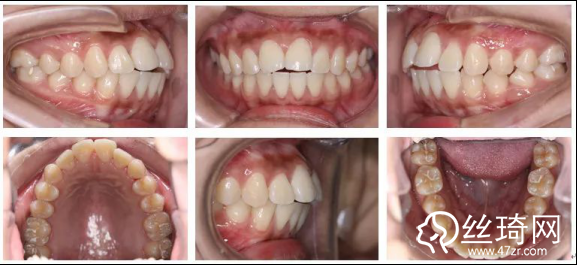

2.* 口內(nèi)檢查(以及調(diào)節(jié)前后口內(nèi)對比):

* 口內(nèi)檢查(以及調(diào)節(jié)前后口內(nèi)對比):

矯正前

口腔衛(wèi)生稍差,軟垢色素(+),牙齦略充血、腫大;恒牙列;左側(cè)磨牙遠中關(guān)系,右側(cè)磨牙中性關(guān)系;前牙開牙合、深覆牙合;上下牙弓尖圓型;上下牙列輕度擁擠;上中線基本正,下中線左偏。

矯正后

上下牙列齊,前牙覆牙合覆蓋正常,中線正,雙側(cè)尖牙及磨牙關(guān)系中性,雙側(cè)后牙尖窩關(guān)系良好。